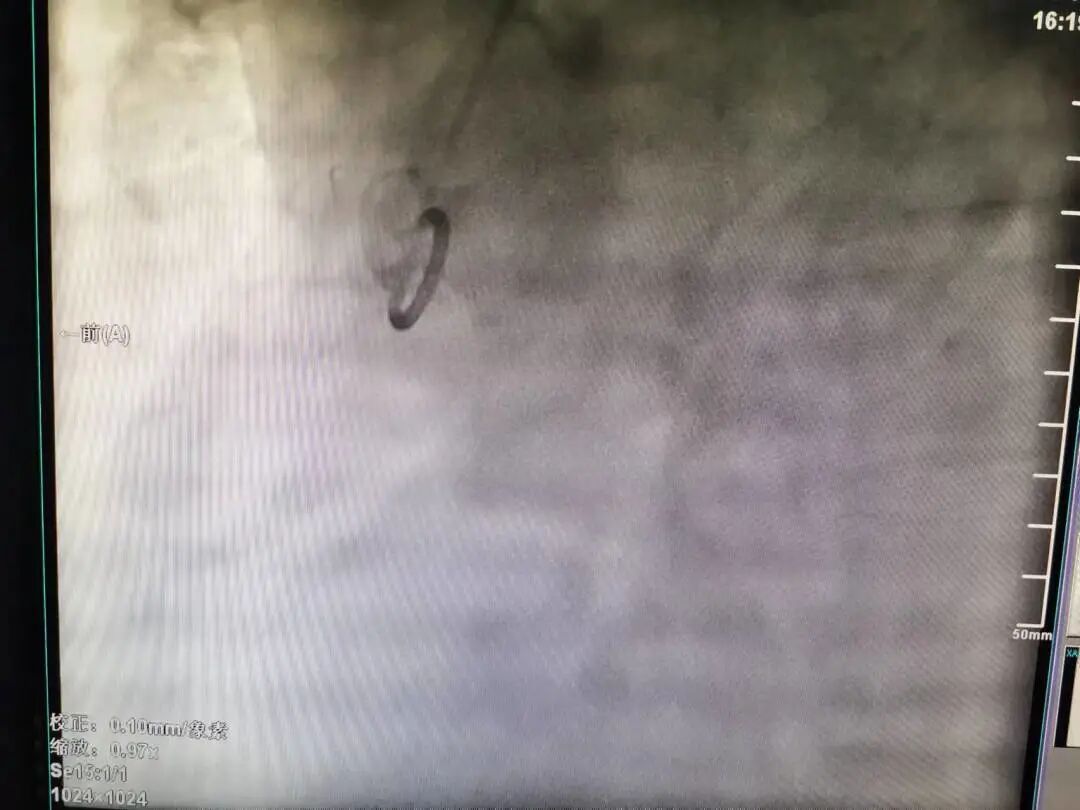

37岁的陈先生,因“胸闷、胸痛4月,加重10天”于11月1日收入我院心血管内科病区,从心电图及心脏彩超结果分析,患者具备冠脉造影的强适应征。郑涛副主任医师仔细查看病人,询问病史、症状,结合体征、检查结果,建议行冠脉造影术,并详细解释手术过程、风险,打消患者顾虑。2022年11月04日行冠脉造影术:术中穿刺右侧桡动脉后造影导管顺利进入左冠脉,造影示左冠状动脉先天性冠状动脉瘘,并可见左冠向右冠远端的逆向血流,而因患者主动脉弓异常扭曲,常规造影导管及专用右冠造影导管反复尝试多次均无法找到右冠脉开口,考虑患者的右冠状动脉开口变异,遂使用猪尾巴导管链接高压注射器造影后隐约显示右冠开口位置,因造影耗时近2小时,为保证患者安全,暂时先下台,准备再次择期手术。

造影导丝是什么再克技术堡垒  巧破闭塞病变——心血管内科应用平行导丝技术救治冠脉慢性完全闭塞患者!_https://www.jmylbn.com_新闻资讯_第3张

猪尾巴导管高压注射器造影隐约显示右冠开口位置